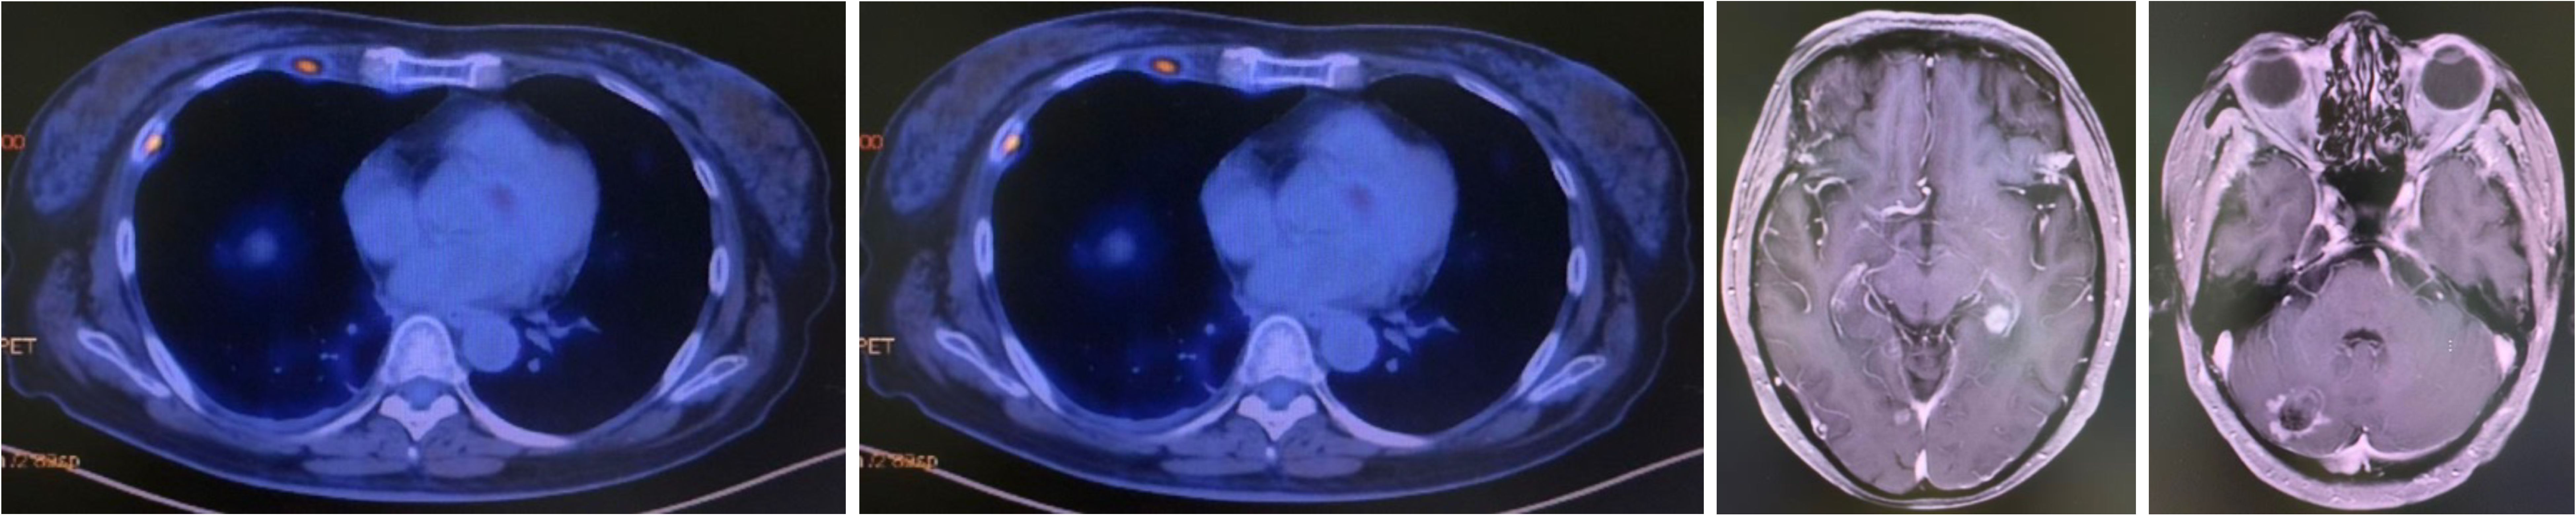

A CT-guided biopsy revealed transformation to small-cell lung cancer with maintained neuroendocrine marker expression. Second-line therapy with etoposide (100 mg/m² days 1-3) and cisplatin (75 mg/m² day 1) was administered for four cycles (9). CT scans showed that the lung lesions had significantly shrunk. (Figure 2) The patient subsequently received consolidative radiotherapy: whole-brain radiotherapy (39 Gy in 13 fractions) followed by intensity-modulated radiotherapy to the primary lung tumor (45 Gy in 30 fractions) (10, 11). Histological analysis from a re-biopsy of the progressive chest lesion revealed small cell cancer transformation and tested positive for neuroendocrine markers, including synaptophysin, chromogranin A, and CD56. Tissue and blood samples were subjected to next-generation sequencing (NGS), which revealed an EGFR exon 21 L858R deletion. In March 2021, PET/CT and brain MRI revealed new metastatic lesions in the pleura and liver capsule, with an increase in multiple metastatic tumors in the brain. (Figure 3) Serum tumor markers showed elevated carcinoembryonic antigen (CEA) (8.1 ng/mL) while NSE remained normal (11.3 ng/mL). Following disease progression, a third biopsy of the chest mass was performed, but no tumor tissue was detected. Circulating tumor DNA (ctDNA) from peripheral blood revealed an EGFR exon 21 L858R deletion. We considered that the recurrent focus might be adenocarcinoma of the lung. Plasma ctDNA analysis confirmed persistence of EGFR L858R mutation without additional resistance alterations. Third-line therapy (from April 20 to July 21, 2021) with paclitaxel (200 mg/m²), carboplatin (AUC 5), and bevacizumab (15 mg/kg) was administered every three weeks (12). After four cycles, CEA decreased to 3.9 ng/mL, and CT imaging showed a partial response (Figure 4). Treatment was complicated by grade 2 epistaxis, leading to bevacizumab discontinuation. The patient was switched to maintenance therapy with aumolertinib (110 mg daily) combined with anlotinib (12 mg daily, days 1–14 every 21 days) (13, 14). Follow-up assessments at 2, 6, 10, and 14 months showed sustained clinical and radiographic stability. The patient ultimately died due to progressive brain metastases in November 2022, with an overall survival of 48 months. The course of treatment is presented in Figure 5.

Figure 3

Medical imaging showing two PET scans and two MRI brain scans. The PET scans display cross-sections of the chest with highlighted areas. The MRI scans present detailed axial views of the brain, indicating varied intensity regions.

Figure 3. Progression after chemotherapy holiday since October 2020.